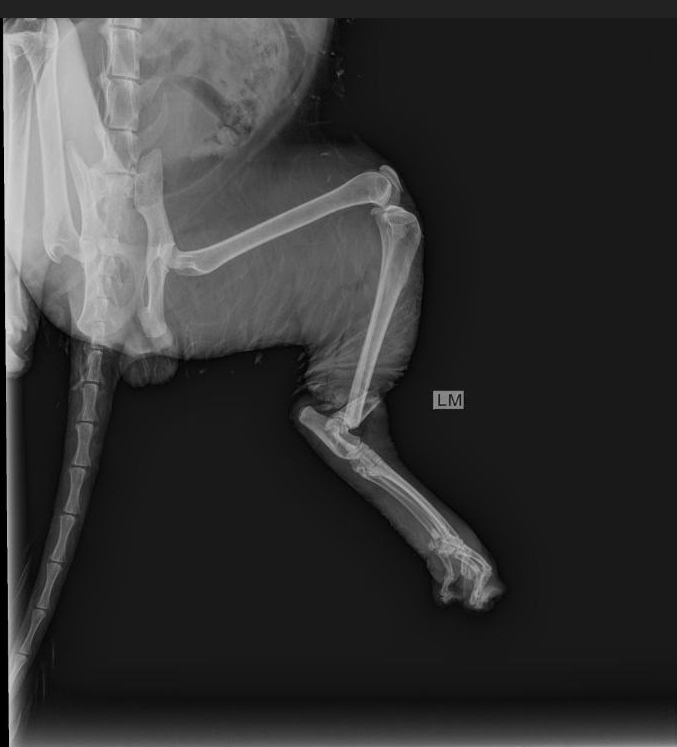

Экстренно!!! нас ждут в клинике, уличный кот, попал в капкан,котику очень больно,очень сильно кричит,нога болтается,открытый перелом берцовой кости.